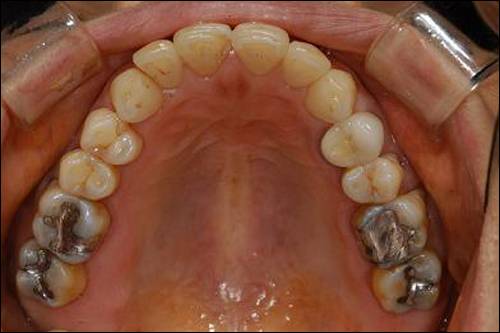

앞니가 아닌 어금니(대구치, 소구치)의 충치를 제거하고 수복하는 재료는 일반적으로 '아말감', '레진', '골드 인레이', '심미(레진, 세라믹 등) 인레이' 이렇게 4가지인데 이 중 유일하게 건강보험의 적용을 받는 재료가 아말감이다.

다음으로 하고 싶은 이야기는 재료로써 아말감의 우수함이다. 컴퓨터로 검색해 본 인터넷의 정보에는 실패한 아말감 케이스들이 나와있었다. 그 사진들만 보고 있으면 '아말감은 정말 가난한 사람들이 어쩔 수 없이 선택하는 도저히 못쓸 싸구려 재료'라는 느낌이 들었다.

아말감의 대체재로 사용하는 복합 레진은 중합 수축이라는 단점이 있다. 적은 양이지만 재료의 끝 부분이 줄어든다는 것은 틈이 생긴다는 의미이고 이것은 2차 우식의 가능성을 높인다. 아말감은 반대로 경화 팽창의 과정을 가진다. 이 점만을 가지고 아말감이 레진보다 좋은 재료라고 말하기는 어렵지만 적어도 나름의 장단점을 가진 재료인 것만큼은 확실하다. 10년 이상의 장기 사용을 하고도 2차 우식이 생기지 않은 케이스가 적지 않음을 생각하면 아말감 역시 정확하게만 시술하면 얼마든지 수복재로써의 기능을 다할 수 있는 재료인 것이다.